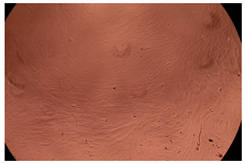

The results of the cytotoxicity assay, given in Figure 5, indicate that the tested PMs at all three established concentrations (10, 50, and 100 µg/mL) did not show cytotoxic effects on fibroblast cells at either 24 or 48 h after incubation. The percentages of cell viability were high, over 90%, in cells that were exposed to a concentration of 10 µg/mL for 24 h for all tested materials. Even at 48 h after incubation, the percentage of cell viability was as high as 90.4% in cells exposed to a concentration of 10 µg/mL for the Cop B sample. For both drug-loaded PMs, the cell viability decreased slightly at all tested concentrations. It also appears that the Dorzolamide-loaded PMs have slightly lower cell viability as compared to IMC-loaded PMs. Micrographs of the fibroblast cells after incubation times of 24 and 48 h are provided in Table 2.

Table 2.

Micrographs of fibroblast cells after 24 and 48 h incubation times, respectively.

As the cell viability values are all over 80%, the results indicate that the PMs, at the established concentrations, can be used successfully for in vivo biomedical applications.